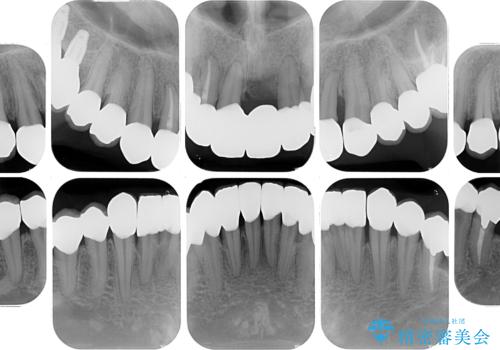

- かかりつけ医にて歯周病治療の名目で治療を行っていたものの、治療プランが明確でないままにインプラント処置を行うとことに疑問を感じ、来院された患者様です。

かかりつけ医では、歯周病治療は終了したため、抜歯を行った右上奥歯にインプラント埋入を行うとの案内があったそうです。

検査を行ったところ、歯周外科処置や抜歯が必要と思われる箇所が散見されたため、あらためて当院に歯周病の初期治療から行うこととしました。